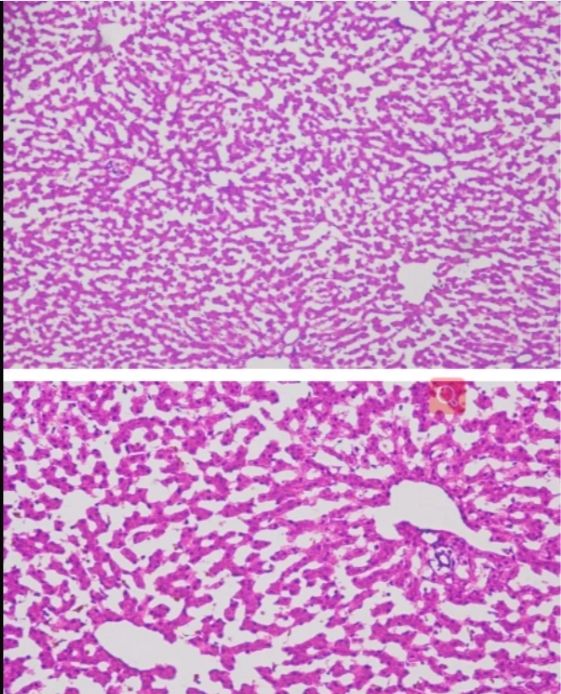

冰凍切片實驗是生物學、醫學等領域中常用的一種實驗技術,主要用于觀察和研究生物組織的微觀結構。在進行冰凍切片實驗時,掌握一些關鍵的技巧對于獲得高質量的切片至關重要。本文將詳細分享一些冰凍切片實驗的技巧,幫助讀者更好地進行實驗。